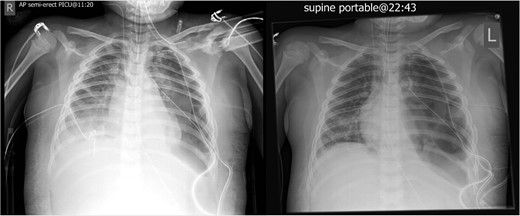

Post operatively, two left sided chest drains were left on free drainage. There were persisting smaller cavities within the left lung. Serial chest radiographs over the next 7 days demonstrated a persisting, increasing left pneumothorax and worsening consolidation of the left lung (Fig. 4). On the 8th post-operative day, the child suffered an acute respiratory deterioration with a reduction in oxygen saturations. The chest radiograph revealed a new right-sided tension pneumothorax which required emergency drainage (Fig. 5).

Worsening appearances of the left pneumothorax despite chest drains in situ.

The cerebellar brain abscess was drained surgically, with pus sent for microscopy and culture. This returned gram negative coliform organisms and pus cells. The antibiotic therapy was modified to account for the new microbial sensitivities. The appearances of both the brain and chest improved over the next 10 days with complete resolution of the intracerebral abscesses and thrombosis (Fig. 8). There was a slower resolution of the chest. The patient was discharged from our institution after 16 weeks.

Eventual complete resolution of the brain abscesses and sinus/ IJV thrombosis.